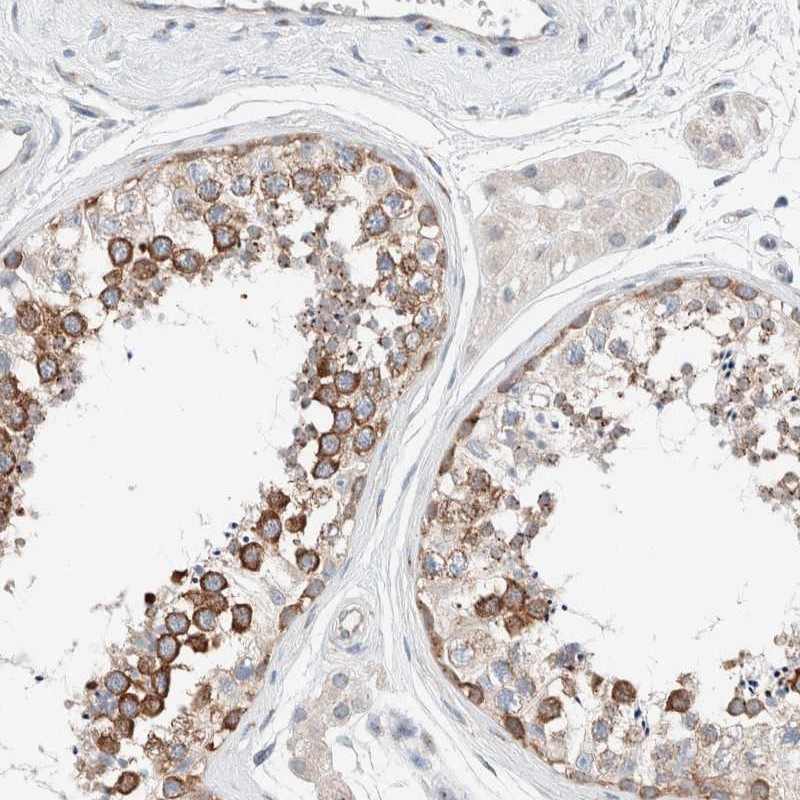

Immunohistochemical staining of human testis shows strong cytoplasmic positivity in seminiferous ducts.